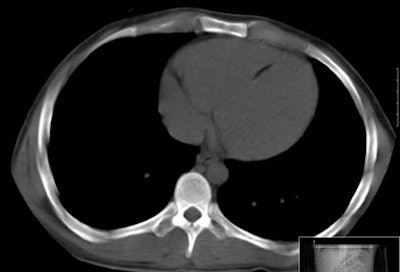

The study revealed foci of fat attenuation within the myocardium in 35 (64%) of 55 patients with TSC. Ranging in size from 3 x 1 mm to 62 x 31 mm, the fat was well circumscribed and focal. The majority of foci were found in the interventricular septum and left ventricle wall, with a few others in the right ventricle wall and papillary muscles.

"This location differs from intramyocardial fat in the right ventricle that has been described in healthy patients and in patients with arrhythmogenic right ventricular dysplasia (ARVD)," they wrote.

In addition, ARVD patients show a more diffuse fat infiltration as opposed to the focal mainly ovoid fatty foci seen in TSC patients in the study, they noted. No enhancing regions were seen in the fatty foci in TSC patients, in contrast to foci seen in patients with primary cardiac hemangioma.

| Myocardial fat in patient with tuberous sclerosis complex at CT. Image courtesy of Dr. Miraude Adriaensen. |

Only one individual in the control group (34-year-old woman) had a thin curvilinear hypoattenuated lesion in a subendocardial location, which might be suggestive of prior myocardial infarction.

"Despite incomplete depiction of the heart with CT, the majority of patients with TSC demonstrated well-circumscribed foci of fat attenuation in the myocardium that were not present in age- and sex-matched control subjects," Adriaensen and colleagues wrote. "This suggests that such fatty foci may be another characteristic of TSC."